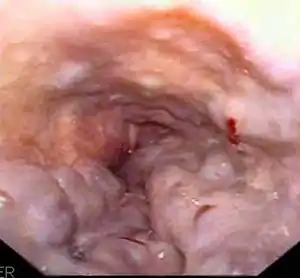

Esophageal varices are extremely dilated sub-mucosal veins in the lower third of the esophagus.[1] They are most often a consequence of portal hypertension,[2] commonly due to cirrhosis.[3] People with esophageal varices have a strong tendency to develop severe bleeding which left untreated can be fatal. Esophageal varices are typically diagnosed through an esophagogastroduodenoscopy.[4]

| Gastroscopy image of esophageal varices with prominent cherry-red spots | |

Dilated submucosal veins are the most prominent histologic feature of esophageal varices. The expansion of the submucosa leads to elevation of the mucosa above the surrounding tissue, which is apparent during endoscopy and is a key diagnostic feature. Evidence of recent variceal hemorrhage includes necrosis and ulceration of the mucosa. Evidence of past variceal hemorrhage includes inflammation and venous thrombosis.